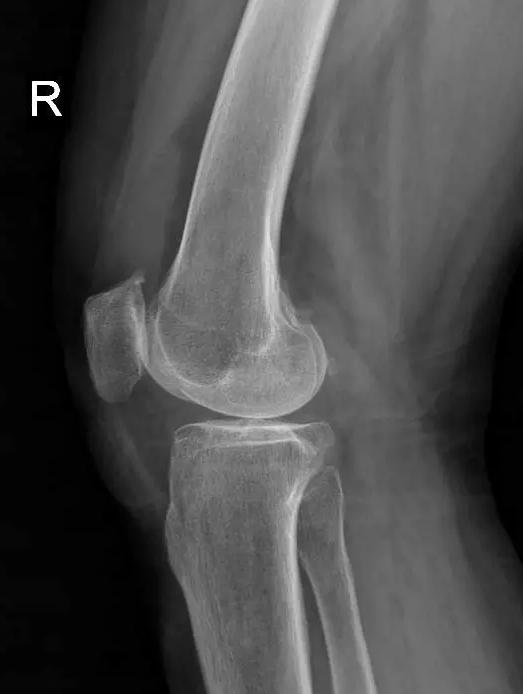

术前片:

对于晚期(重度)骨关节炎,保守治疗无效时,要积极考虑手术治疗。目前效果最佳的手术方式即为关节置换手术,其他手术方式如关节融合手术等效果较关节置换术相差较大,已不在临床广泛使用。关节置换手术的目的是缓解患者疼痛,矫正关节畸形,恢复关节功能,恢复正常生活。对于老年人来说,积极的手术治疗可以有效恢复其日常生活,避免因疼痛及活动障碍导致患者扶拐或坐轮椅,有效减少因缺乏运动导致的心肺功能障碍及精神问题发生。经过几十年的发展,目前关节置换技术已十分成熟,临床上目前采用的微创技术,手术创伤小,术中出血非常少,术后第二天患者即可下地行走,三月之后即可恢复正常生活及功能。至于人工假体使用寿命,目前进口关节多为20-30年,能满足60-70岁患者的需求。需要注意的是,在行关节置换手术之后,患者仍需要进行积极的康复治疗,包括关节活动度及周围肌力的锻炼等,这样才能达到最佳的手术效果。

晚期:骨关节炎表现为膝关节明显疼痛,休息后常无缓解,伴有活动受限,可并发畸形,X 线片可见关节周围有明显的骨赘形成,或可见游离体,关节间隙明显狭窄,甚至消失。